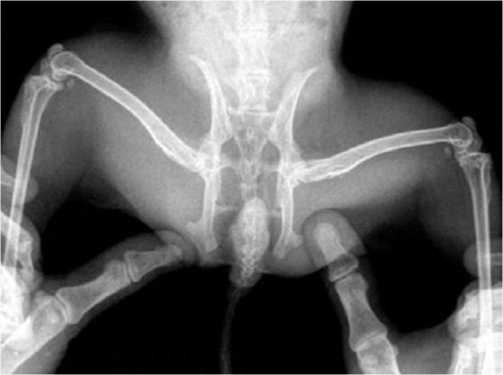

Рис. 1. Обзорная рентгенография тазобедренных суставов экспериментального животного на десятые сутки после хирургического лечения путём криовоздействия 3 секунды.

На 10-е сутки после проведенных оперативных вмешательств интраоперационно под наркозом был иссечен сформировавшийся регенерат в области туннеля проксимального отдела бедренной кости. Визуально определялись светлые плотно-эластичные белесоватые наслоения, внешне напоминающие соединительную ткань. Перед иссечением криорегенерата животному было проведена обзорная рентгенография тазобедренных суставов (Рис. 1).

Однако в условиях эксперимента на животных малых размеров рентгенографические методы исследования малоинформативны и низкодоказуемы, поэтому наиболее предпочтительными являются микроскопические способы доказательства эффективности предложенной методики. Далее проведен забор криорегенерата с использованием глазного скальпеля Optimum и микроложечки фолькмана из области туннеля шейки бедренной кости для проведения морфологических исследований (световая и электронная микроскопия). Помимо забора криорегенерата был произведен забор материала из туннеля шейки бедренной кости животных группы сравнения, не подвергшихся дополнительному криовоздействию. Гистоморфологическое исследование регенерата группы сравнения демонстрирует обычное образование первичной костной мозоли через развитие хрящевой и соединительной ткани. Далее представлены микроскопические исследования зоны криорегенерата в условиях модели АНГБК. Наиболее информативная